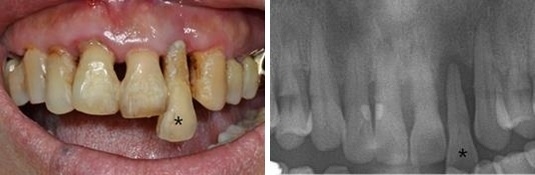

초기에 잇몸에만 국한된 염증을 ’치은염(Gingivitis)‘이라고 하며, 적절한 치료가 되지 않아 염증이 심해지면 ’치주염(Periodontitis)‘으로 발전하게 된다. 이때에는 치조골 파괴와 치은퇴축(잇몸조직의 상실로 인해 치아뿌리가 노출되는 것)이 일어나게 되며 심한 경우 치아동요(치아가 좌우 또는 상하로 흔들리는 것)를 유발하고 결국 치아상실까지 초래한다.

치주염은 염증이 잇몸을 넘어서서 치조골까지 확장되어 치아가 흔들리며 잇몸이 내려가게 되고, 시리거나 음식을 씹을 때 힘이 없는 느낌 또는 통증이 발생한다. <위 사진>

대부분의 환자들은 치아가 흔들리거나 통증이 발생한 후에야 치과에 방문하는데, 이런 경우 이미 적절한 치료시기가 지나서 치아를 뽑아야 하는 안타까운 상황이 발생하는 경우가 많다.